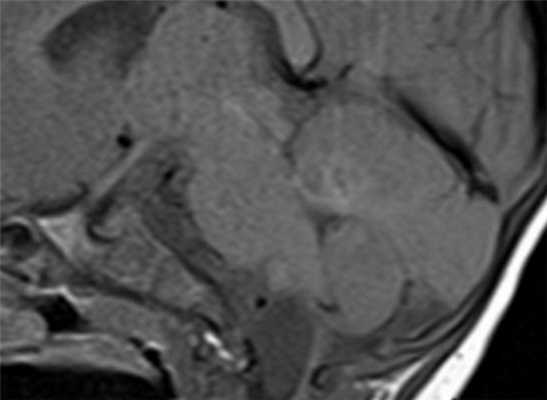

МРТ головного мозга. Корональная Т1-взвешенная МРТ. Многокамерные эхинококковые кисты.

Киста кармана Ратке представляет собой редко встречающееся образование из остатков эмбриональной эктодермы (щель Ратке), расположенное между долями гипофиза. Выявляется в любом возрасте, но чаще в 50-60 лет. Клинические проявления связаны с масс-эффектом. При МРТ головного мозга выявляется небольшая (3-5мм) киста с четким контуром, без отека вокруг, однородная по структуре. Сигнал на МРТ головного мозга зависит от содержимого. При серозном содержимом сигнал типично жидкостный, при мукоидном киста светлая на Т1-взвешенных МРТ головного мозга. В 70-80% случаев внутри кисты выявляется неконирастирующийся узелок («пятно») - признак патогномоничный для кисты кармана Ратке. В редких случаях киста достигает больших размеров и даже выходит за пределы седла. Стенка кисты иногда усиливается при МРТ головного мозга с контрастированием. Дифференциальная диагностика при МРТ головного мозга должна проводиться с арахноидадьной и эпидермоидной кистами, тератомой, кистозной аденомой гипофиза и краниофарингиомой. Иногда при МРТ головного мозга киста кармана Ратке напоминает “пустое” турецкое седло. При маленьких размерах кисты ее на до дифференцировать на МРТ с микроаденомой гипофиза.

![Ratke cleft cyst]()

МРТ головного мозга. Т1-взвешенная сагиттальная МРТ. Киста кармана Ратке.